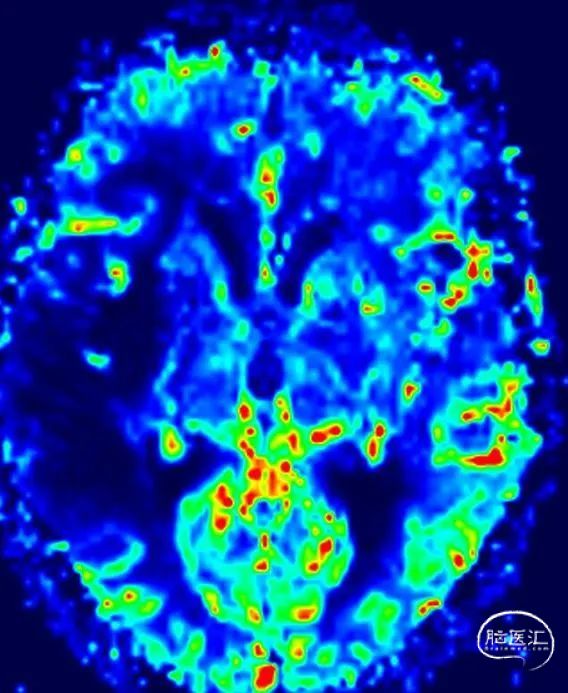

MR灌注

MTT